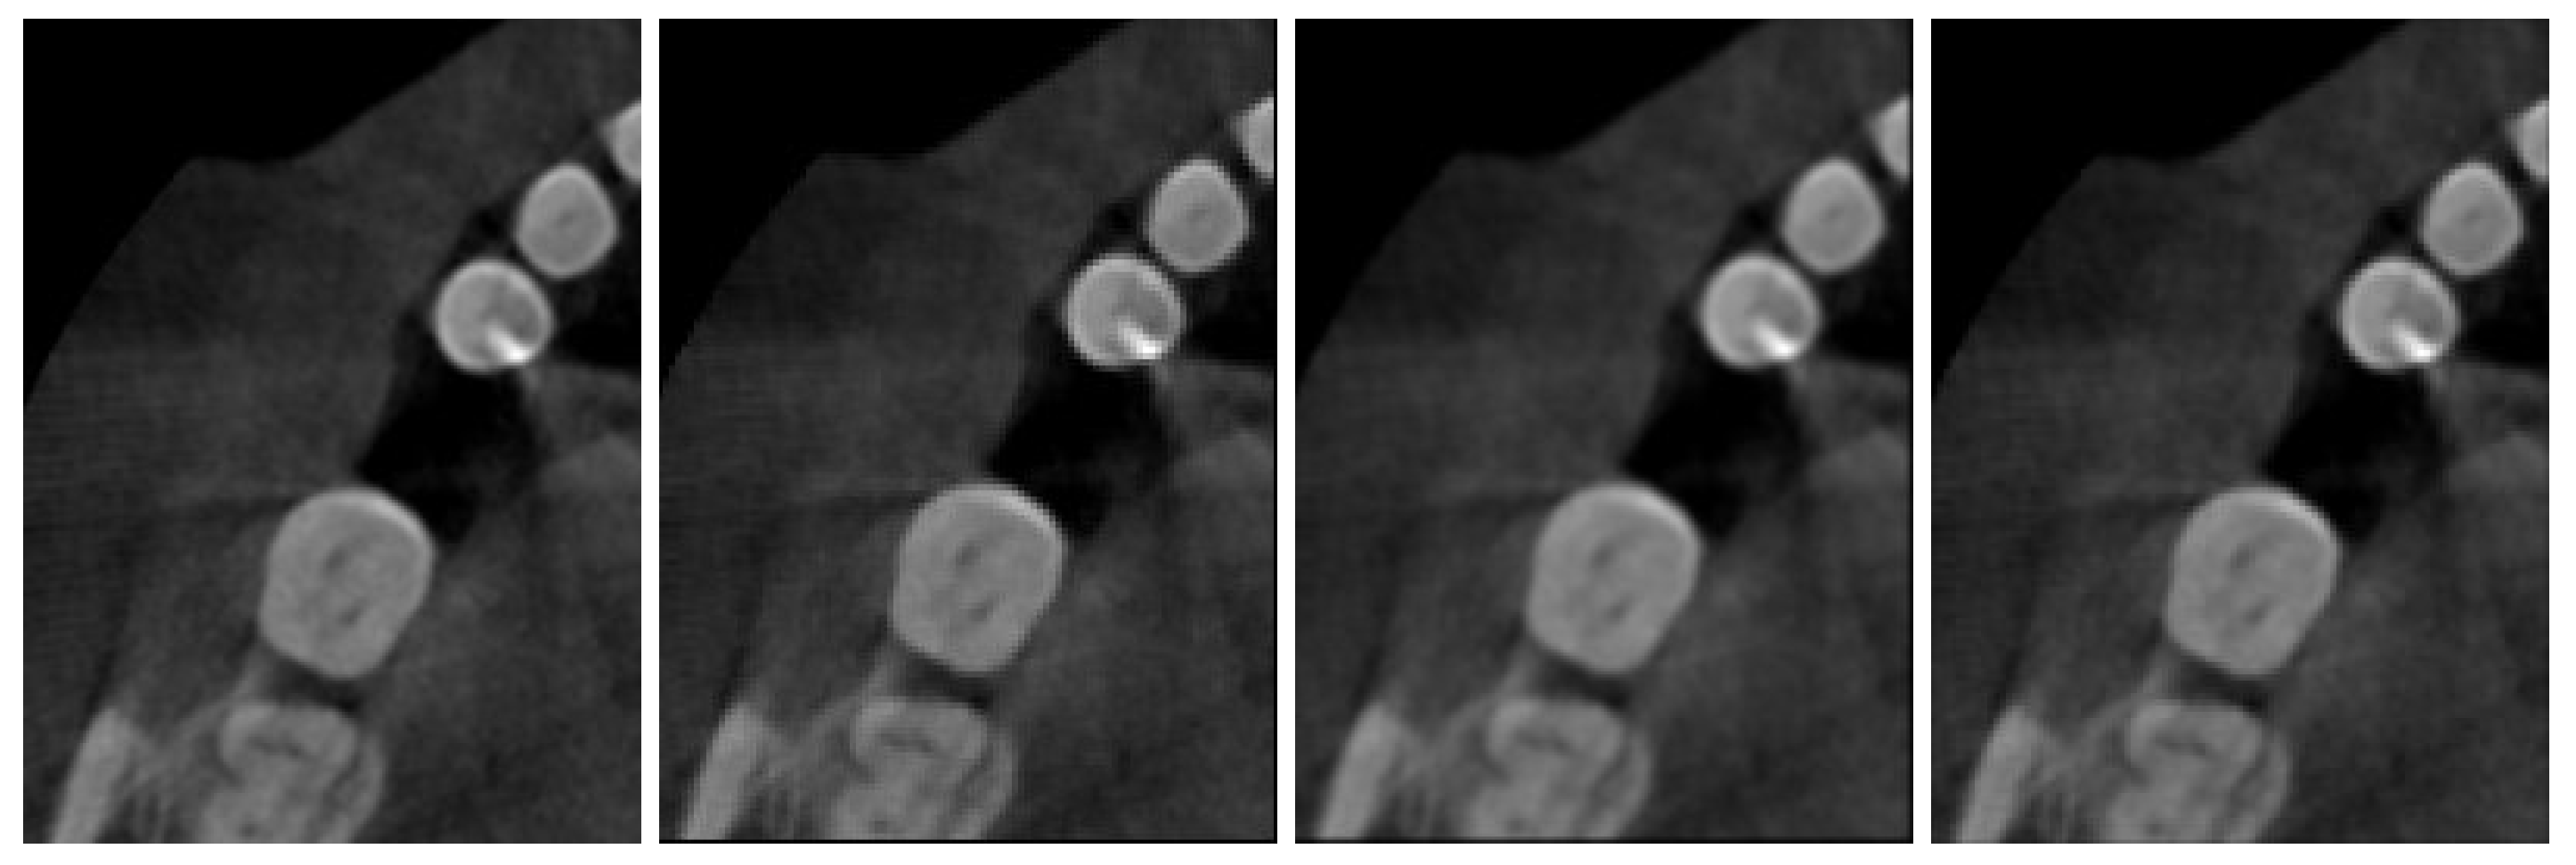

3. Numerical Results